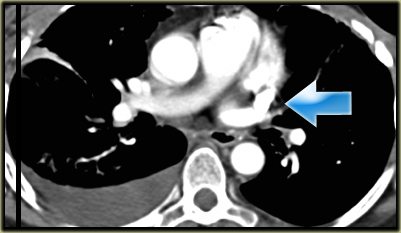

Left Superior Intercostal Vein.

This is an anastomosis between the accessory hemiazygos vein and the left brachiocephalic vein.

It courses along the lateral margin of the aortic arch (‘aortic nipple’).

It is a normal variant and if you look for this structure you will frequently notice it.

On the left a patient with a left superior intercostal vein.

Notice the ‘aortic nipple sign’.

On the left another example of a left superior intercostal vein.

It courses along the lateral margin of the aortic arch from the the accessory hemiazygos vein to the left brachiocephalic vein.